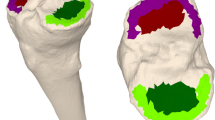

Accuracy

The available postoperative CT scans of the ten selected patients in this study were used to test the accuracy of the tool. Coronal and sagittal alignment—corresponding to rotation along the x- and y-axis in the tool, respectively – were calculated in a 3D reconstruction of the tibias with tibial TAR components. The 3D reconstructions were created by segmenting CT scans in Mimics (Research 22.0; Materialise NV, Leuven, Belgium). TAR alignment was measured by obtaining the angle between the tibial axis and the plateau of the tibial TAR component. The tibial axis was obtained by finding the centroids along the tibial shaft and fitting a line through these centroids (Fig. 5) [26]. The tibial plateau was obtained by fitting a line along the bottom plateau of the tibial TAR component. The angle between the tibial axis and tibial TAR in the coronal and sagittal plane is regarded as the true TAR alignment. The percentage of accuracy was calculated using \(\%\;accuracy=(1-abs\left(\frac{{V}_{A}-{V}_{O}}{{V}_{A}}\right))*100\%\) with \({V}_{A}\) being the accepted value obtained from the 3D reconstruction, and \({V}_{O}\) being the outcome obtained from the semi-automatic tool.